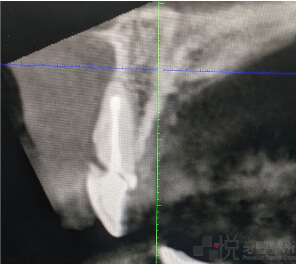

在植牙前,請患者拍攝電腦斷層 (3D 的連續電腦斷層掃描),後續再將檔案匯入到 X-Guide 的電腦軟體當中建模設計植體位置,讓手術醫師在手術時操作 X-Guide 有畫面依據去「即時導航」。

張先生吃飯時太急咬到筷子牙齒因而斷裂前來就診,我們在拔除斷牙後,立即植牙同時在拔牙窩洞的空隙填上骨粉。植好牙的同時,再利用原來的斷牙作為臨時假牙,黏附在鄰牙以維持美觀及發音。

如果採用導引板植牙,傳統導引板或是數位設計出來的 3D 導引板,在前牙即拔即種的案例,最難克服的就是導引板容易位移上翹。經驗不足的話容易左右位置很準,但是植牙的牙度向前偏斜(暴牙),偏斜角度太大還有可能要重新取出植體,或是假牙的製作受限無法滿足美觀需求。

X-Guide 植牙導航機則可以即時在畫面中看到手術時的深度、位置、角度,而且可以即時校正,不斷確認裝置位置是否有移位,是最適合用在前牙立即植牙的最佳輔助工具。